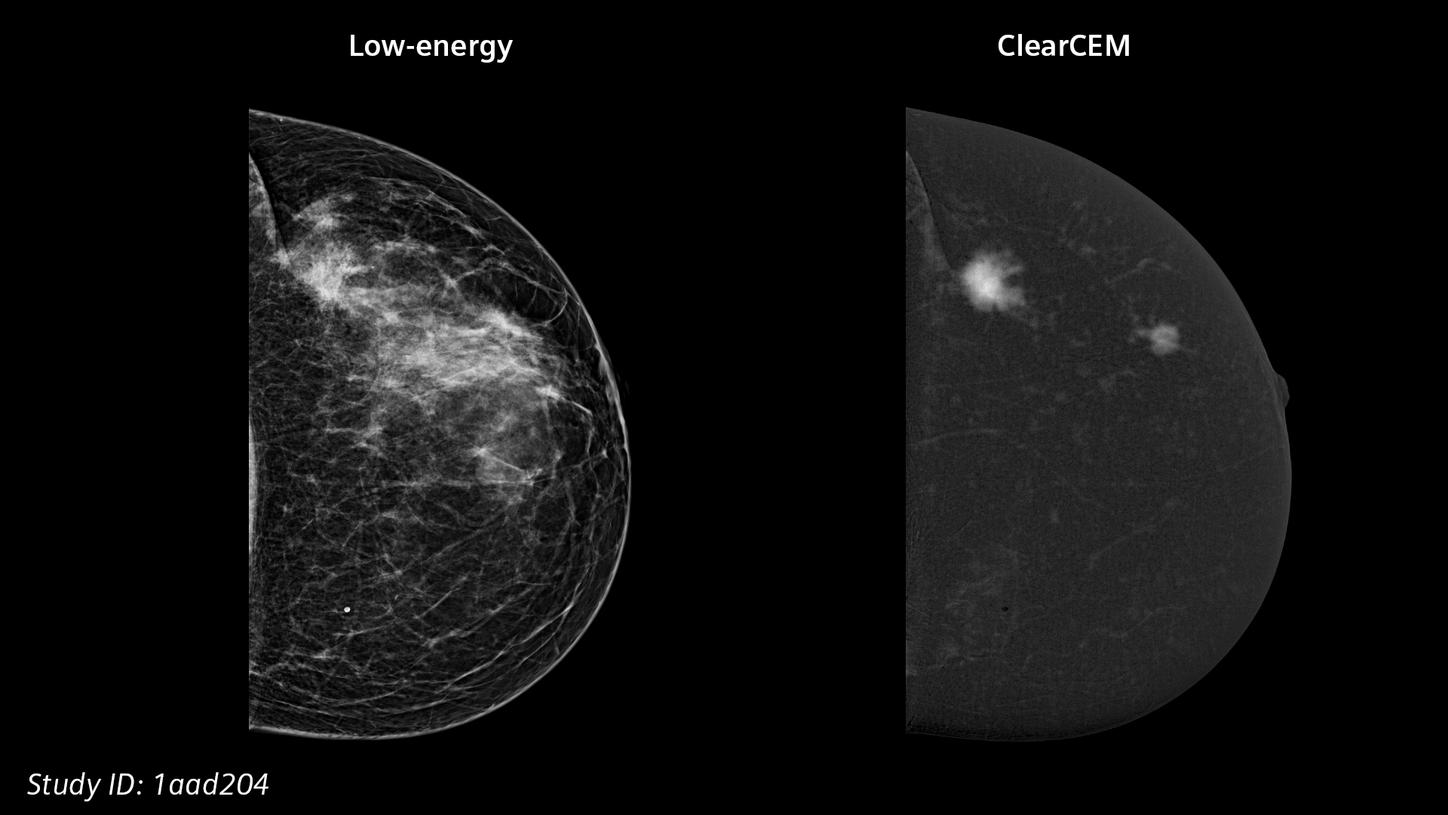

Our new recombination algorithm lifts CEM (contrast-enhanced mammography) breast imaging to a higher, brilliant level: with outstanding image quality, we are setting a new benchmark for accuracy and diagnostic certainty, bringing mammography closer to MRI.

ClearCEMA new era in contrast-enhanced mammography